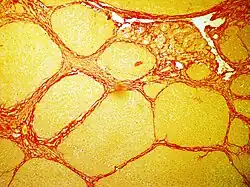

In histology, sirius red staining is used in various domains of diagnostic to observe fibrosis levels in a lot of cases of inflammation induced by cancer, vascular or metabolic pathologies.[2]

In bright field microscopy the following can be observed:

- The nuclei in yellow

- The cytoplasm in yellow

- Collagen fibers in red

- Muscular fibers in yellow

- Red blood cells in yellow